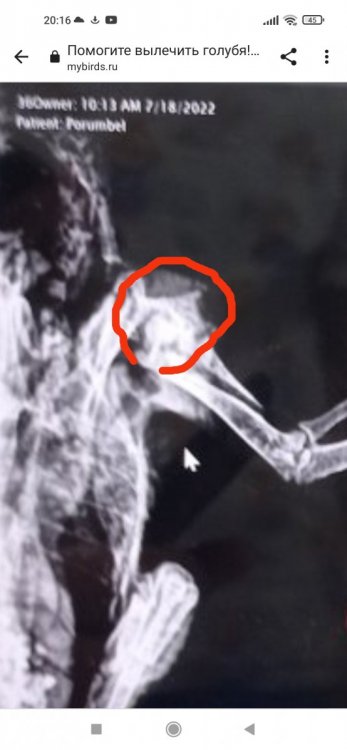

Cabrera Опубликовано 23 июля, 2022 #147 Опубликовано 23 июля, 2022 10 минут назад, kiskonatala0310@gmail.com сказал: Как Вы думаете,стоит его приподымать и опускать для разработки крыла или ещё рано Нет, ещё рано, по рентгену плечевая кость ещё даже срастаться не начала. Вам же врач написал, что ограничение подвижности минимум дней 40. 2